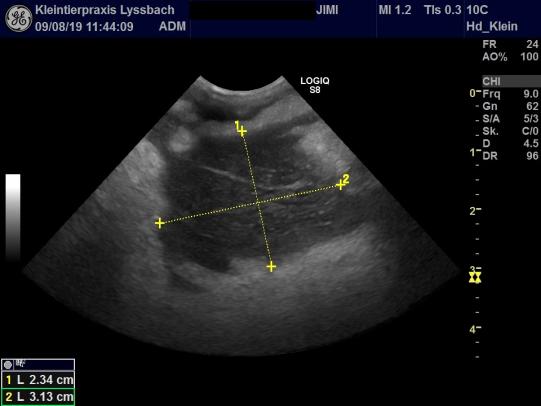

Mittels Ultraschall wird die Gegend untersucht. Tatsächlich findet sich eine grosse Kammer mit freier, stark echogener Flüssigkeit, welche wir punktieren: Zu unserer Überraschung finden wir aber nicht Blut, sondern eindeutig Eiter! Ganz offensichtlich hat sich an dieser seltsamen Lokalisation ein grosser Abszess gebildet.